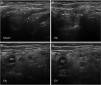

Nerve ultrasoundNerve ultrasound is currently a routine diagnostic technique for studying PNS conditions.93 In our series of 6 patients with early GBS (4 AIDP and 2 AMSAN), the main alterations observed in ultrasound studies involved the ventral rami of the cervical nerves, and consisted of enlarged cross-sectional area, loss of the hyperechoic epineurial rim, or both (Fig. 8).15,94 Only 8.8% of peripheral nerve trunk ultrasound studies detected inflammatory alterations, with the median nerve most commonly affected.

Ultrasound image of cervical nerves from a patient with AIDP (the same patient as Figs. 2 and 3); figures and S1 from Gallardo et al.15 show histology findings from the sixth cervical nerve.

A) Sagittal ultrasound image showing blurring of the epineurial covering of all 3 nerves scanned (callipers). The asterisks indicate the transverse processes.

B-D) Short-axis ultrasound images of the ventral rami of nerves C5-C7 (dotted green tracings). The nerves show significantly enlarged cross-sectional areas. Note the lack of a hyperechoic epineurial rim; this may be compared against the images published in the normative study by Haun et al.94 The endoneurial inflammatory oedema (see Fig. 2C-D and 3) explains the enlarged cross-sectional area, while the epi-perineurial inflammatory process (see Fig. 2E) would account for the blurring of the hyperechoic epineurial rim.

In contrast to our findings, other authors do report enlarged cross-sectional areas of peripheral nerve trunks in early GBS, although only regressive oedema of nerves C5 and C6 seems to correlate with clinical improvement.95–97 Given the importance of the examiner’s skill in nerve ultrasound studies, further research is needed to more precisely determine the technique’s usefulness as a diagnostic test for GBS.98,99